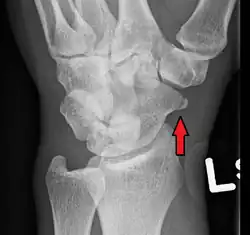

A subtle scaphoid fracture

Scaphoid fractures are often diagnosed using plain radiographs and multiple views are obtained as standard.[9] However, not all fractures are apparent initially.[7] In 1/4 of cases, the clinical examination suggests a fracture, but the X-ray does not show it, even though there is indeed a fracture.[10] Therefore, people with tenderness over the scaphoid (those who exhibit pain to pressure in the anatomic snuff box) are often splinted in a thumb spica for 7–10 days at which point a second set of X-rays is taken.[7] If a minimally displaced fracture was present initially, healing will now be apparent. Even then a fracture may not be apparent. A CT Scan can then be used to evaluate the scaphoid with greater resolution. The use of MRI, if available, is preferred over CT and can give one an immediate diagnosis.[11] Bone scintigraphy is also an effective method for diagnosis fracture which do not appear on Xray.[12]